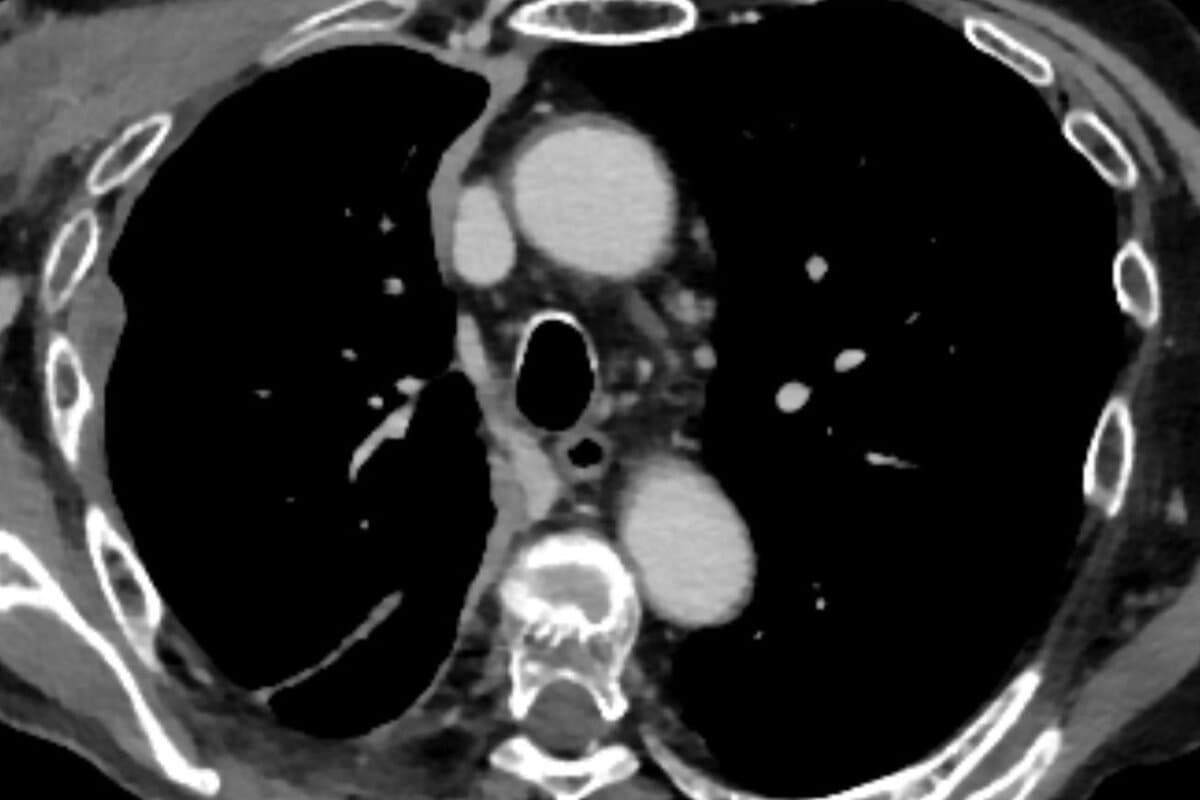

In der MARS-2-Studie erhielten fitte Erkrankte mit resektablen Mesotheliomen eine operative Pleura-Dekortikation plus bis zu sechs Zyklen Platin-Pemetrexed, zwei davon neoadjuvant. Die Kontrollgruppe bekam ausschliesslich die Chemotherapie.